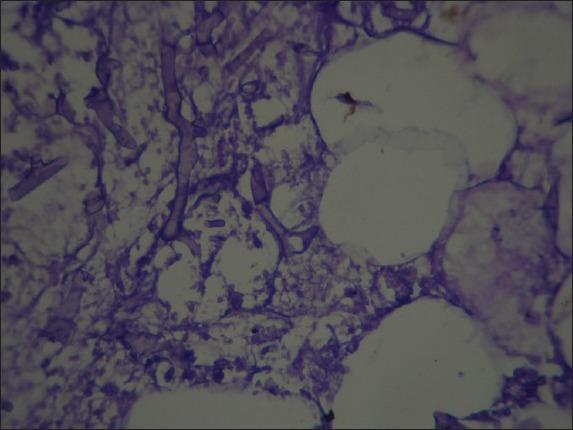

Disseminated mucormycosis is a rare entity most frequently seen in neutropenic patients with hematologic malignancies, post transplants or in patients on deferoxamine therapy. We report a 64-year-old immunocompetent male with an acute pneumonia and a generalized jaundice who died within 24 h. In the autopsy, extensive perforations of spleen and multiple hemorrhage foci on the pancreas were two significant findings. Histopathological study of tissue sections revealed typical zygomycetes hyphae in the left lung, pancreas, spleen and brain. Involvement of pancreas in this patient was one of the rare features of mucormycosis reported occasionally in the literature. Our case implies an unusual clinical presentation of disseminated mucormycosis and highlights that disseminated mucormycosis should be regarded even in the immunocompetent patients.

播散性毛霉菌病是一种罕见疾病,多见于患有血液系统恶性肿瘤的中性粒细胞减少患者、移植后患者或接受去铁胺治疗的患者。我们报告一例64岁免疫功能正常的男性,患有急性肺炎和全身黄疸,在24小时内死亡。尸检时,脾脏广泛穿孔和胰腺多处出血灶是两个重要发现。组织切片的组织病理学研究显示,左肺、胰腺、脾脏和大脑中有典型的接合菌菌丝。该患者胰腺受累是文献中偶尔报道的毛霉菌病罕见特征之一。我们的病例提示播散性毛霉菌病有不寻常的临床表现,并强调即使在免疫功能正常的患者中也应考虑播散性毛霉菌病。